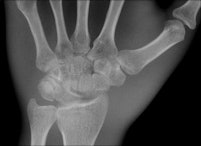

The multifunctional panels can be used in a number of clinical settings, including intensive care for bedside examinations, while portable DR detectors have created new applications in trauma, pediatric, and orthopedic settings.

The industry's first detector featuring wireless image transmission, the DRX-1 from Carestream, was introduced in 2009 at the University Hospital in Frankfurt and subjected to a series of studies by Vogl's group against conventional computed radiography (CR) systems for both image quality and workflow efficiency. As a result of the positive findings from the studies for superior image quality and dose efficiency, the DRX-1 detector is now used as part of routine protocol.

Identical in size to a standard CR cassette, the detector can be inserted into an existing wall stand or table Bucky and used in combination with existing x-ray generators from a number of original equipment manufacturers, presenting an attractive option for modest-budget facilities. The flexibility of the portable detector provides great advantages in time-critical environments where an x-ray image can now be captured and viewed in less than six seconds, he explained.